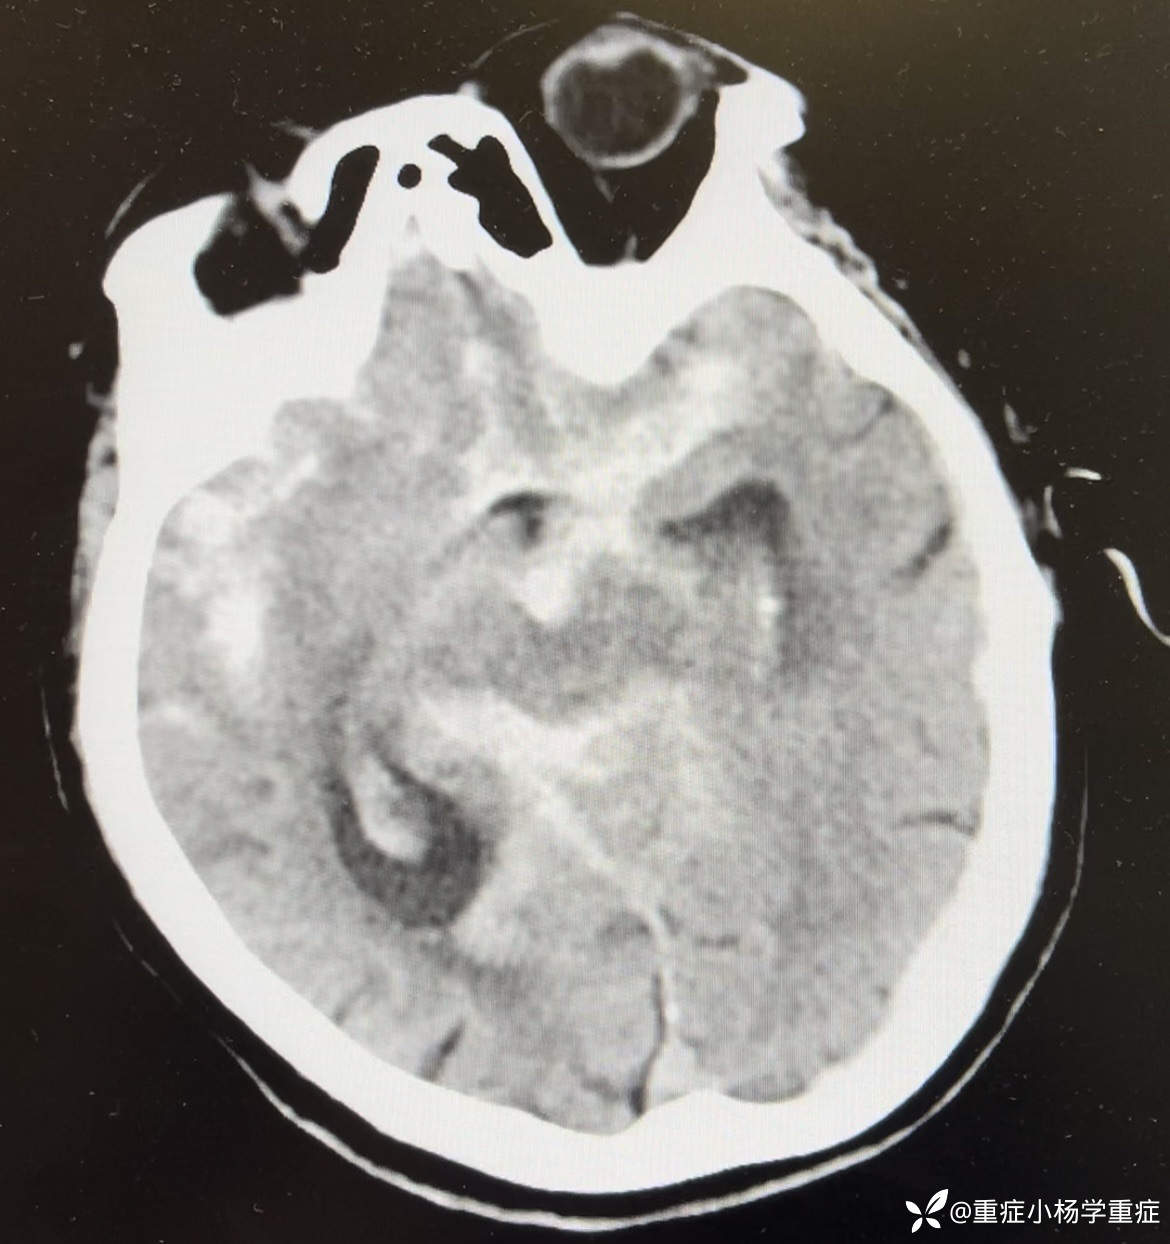

简要病史:患者于7小时余前吃中饭时突发意识不清,头撞到桌面,呼之不应,无抽搐,家属拨打120送我院急诊,测脉搏105次/分,呼吸14次/分,血压:207/92mmHg,SPO2 95%,至急诊后出现呕吐2次,为胃内容物,行CT检查提示:蛛网膜下腔出血破入脑室系统;予以氨甲环酸止血、尼莫地平防止脑血管痉挛、乌拉地尔控制血压,请神经外科会诊考虑“动脉瘤破裂出血”建议行CTA明确诊断及手术治疗,患者家属经商讨后拒绝CTA检查及手术治疗,要求行保守治疗,经我科会诊后以“蛛网膜下出血、脑血管意外、高血压”收住院治疗。

辅助检查:生化:肌酐128.9umol/L↑,钠146.3mmol/L↑。CT平扫:1.蛛网膜下腔出血破入脑室系统;2.老年脑改变;3.考虑两肺少许炎症,随诊复查。